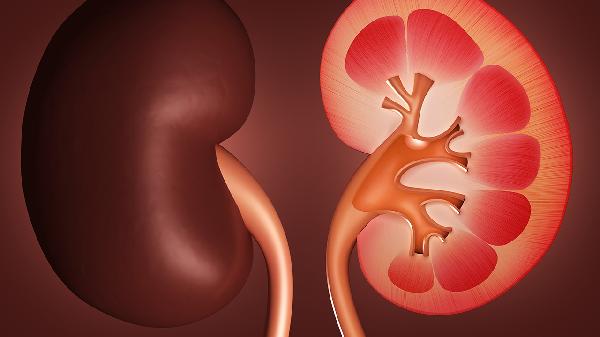

梅毒肾病的症状是什么

梅毒肾病是由梅毒螺旋体感染引起的肾脏损害,早期可能无明显症状,随着病情进展可出现蛋白尿、血尿、水肿、高血压及肾功能减退等表现。梅毒肾病症状主要有蛋白尿、血尿、水肿、高血压、肾功能异常。

5、肾功能异常

晚期可出现血肌酐升高、肾小球滤过率下降,表现为夜尿增多、乏力、食欲减退等。肾功能损害程度与梅毒感染持续时间相关。需评估肾小管功能,警惕急慢性肾功能衰竭,严重时需肾脏替代治疗。